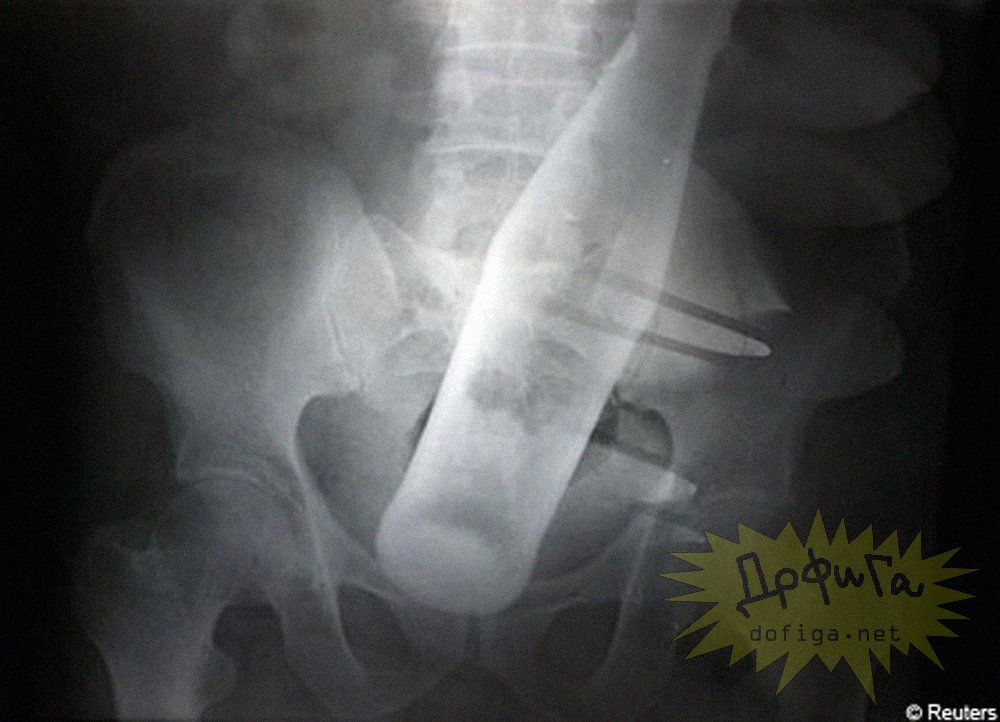

アナルに ”何かしら” を突っ込んで取れなくなってしまう人たちは意外に多いみたいで、そんな人たちのレントゲン写真を集めたギャラリー[13]images